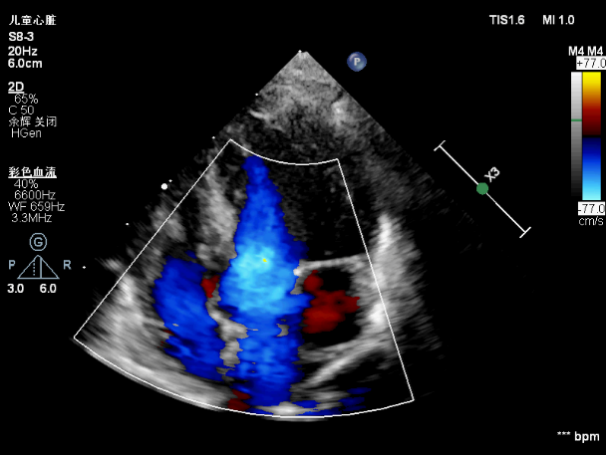

7月19日上午11点40分,孕妇通过剖腹产生下一名体重不到6斤的男婴,出生后宝宝由于缺氧全身呈蓝紫色,呼吸微弱,身体各项指标非常差。心血管超声医学科王斌主任立即床旁急诊超声检查,心脏超声提示:内脏、心房正位,左位心,心室右袢,房室连接一致,心室与大动脉连接不一致,室间隔完整的完全性大动脉转位(S.D.D),细小动脉导管未闭(双向分流),左、右心室发育尚可(见下图)。

左心系统与右心系统仅靠0.2cm动脉导管连接(PA:肺动脉;DA:降主动脉,PDA:动脉导管)